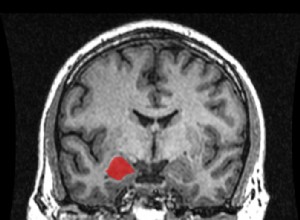

Stimulation cérébrale profonde : une déconnexion ciblée des zones motrices chez les patients parkinsoniens